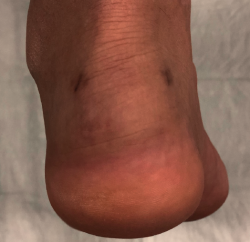

The dorsoplantar and sagittal views of both feet under loading conditions are indicated, together with the posteroanterior view of the ankles under loading conditions.

Figure 3. Plain radiography, Sagittal view with weight-bearing. Moderate calcifications in the insertion of the Achilles tendon with intratendinous enthesophyte. Morphological alterations of the posterior tuberosity of the calcaneus.

Plain radiography under loading conditions is the essential initial diagnostic tool(20). It allows us to assess alignments and dysmetria, to measure angles, to determine the morphology of the calcaneus and its posterior tuberosity, to characterise bone exostosis and increments in thickness of the retrocalcaneal soft tissues, and to plan surgical procedures (Figure 3).